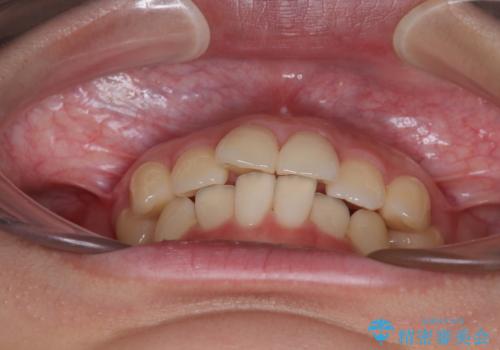

- 上下前歯のデコボコを気にして来院された患者様です。

ワイヤー矯正でもマウスピース矯正でも可能でしたが、短期間で、自身の手を煩わせることなく治療を行いたいとのことで、ワイヤー装置にて矯正治療を行うこととしました。

舌の突出癖により、出っ歯仕上がりとなる可能性がありましたが、舌のトレーニングを頑張っていただき、1年強で終えることができました。